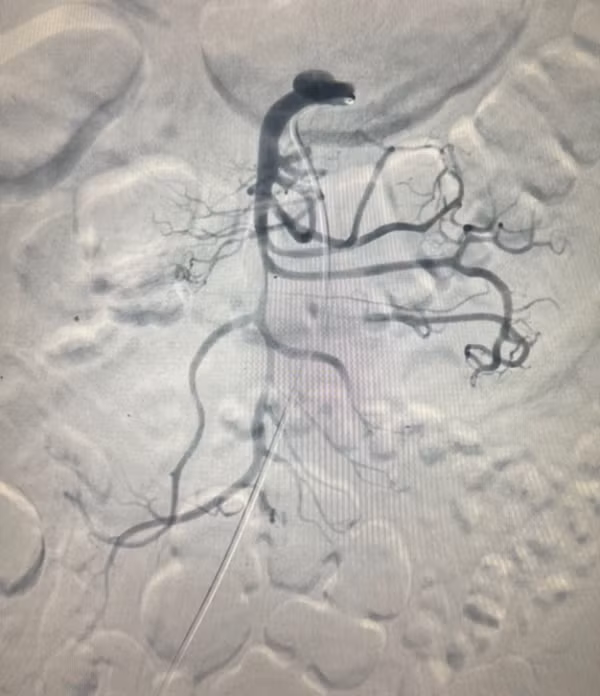

![]() |

| Hình ảnh chụp và can thiệp đặt stent động mạch mạc treo tràng trên: Trước can thiệp bóc tách gần gốc xuất phát, tạo huyết khối gây hẹp lòng và tắc vài nhánh nuôi ruột (hình trái); sau can thiệp đặt stent động mạch mạc treo tái thông hoàn toàn mạch mạc treo, cải thiện tưới máu ruột (hình phải) - Ảnh BVCC |